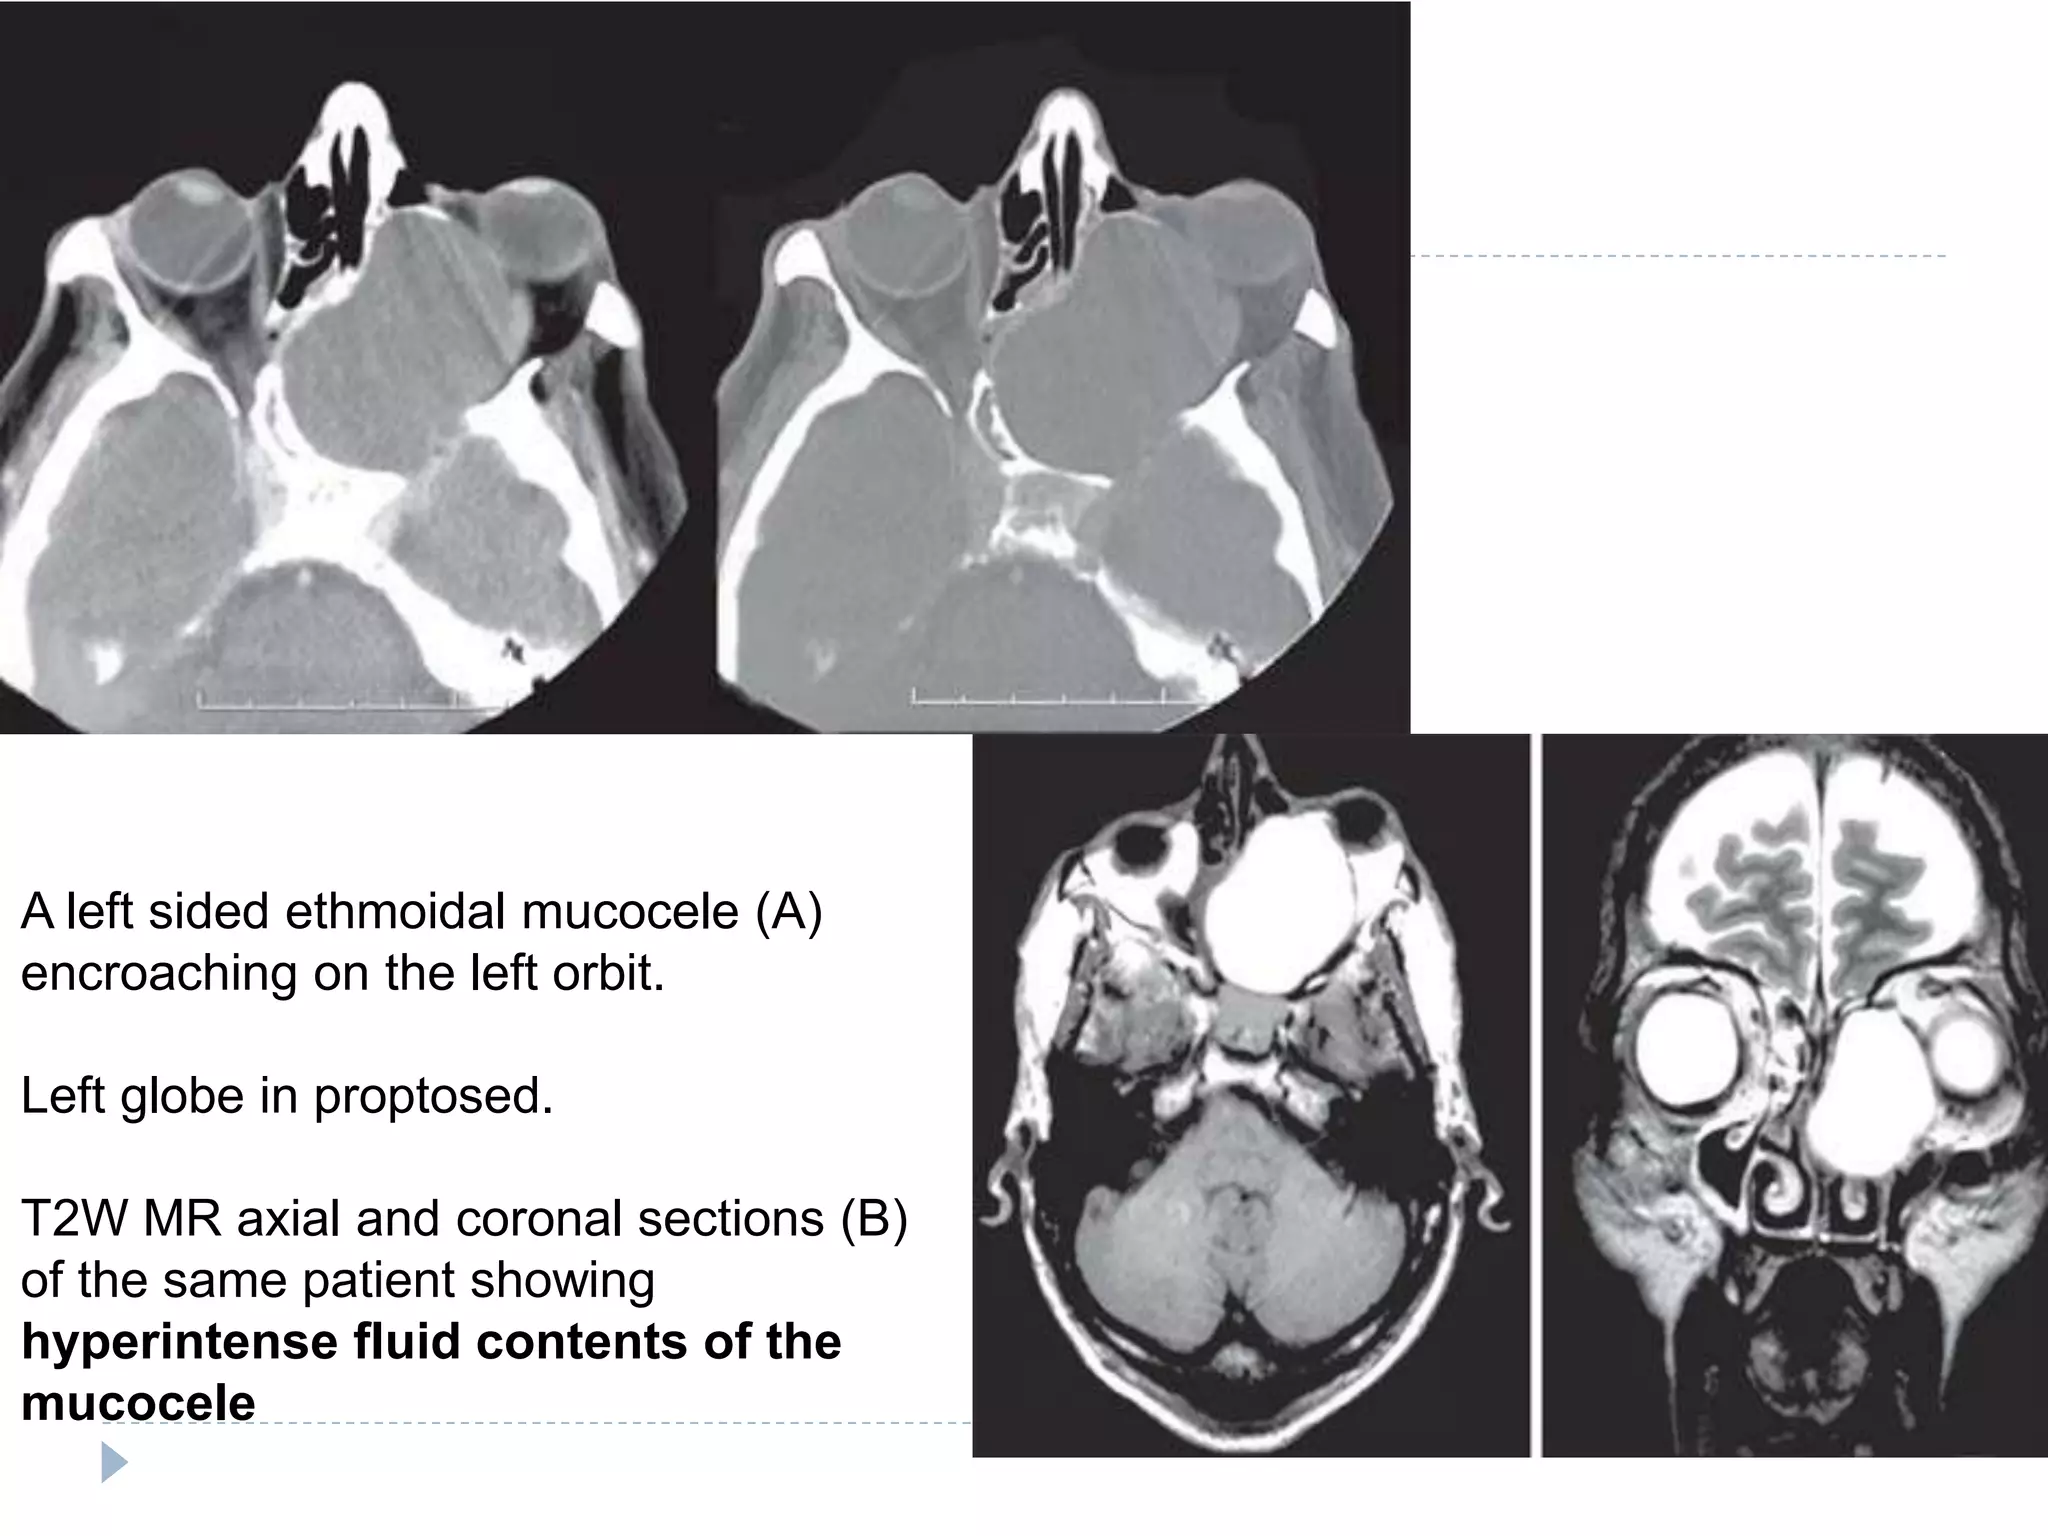

A left sided ethmoidal mucocele (A)

encroaching on the left orbit.

Left globe in proptosed.

T2W MR axial and coronal sections (B)

of the same patient showing

hyperintense fluid contents of the

mucocele